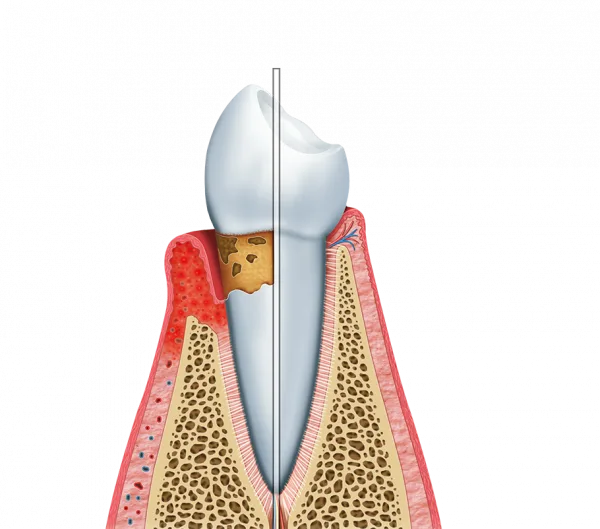

O tratamento periodontal é uma abordagem crucial para a saúde bucal.

Ele se concentra na prevenção e tratamento de doenças que afetam os tecidos de suporte dos dentes.

Essa especialidade odontológica é essencial para manter a saúde da gengiva e do osso alveolar.

O tratamento periodontal promove uma saúde bucal robusta.

Ele ajuda a controlar inflamações e a remover tártaro acumulado.

Além disso, a limpeza profunda das gengivas reduz o risco de infecções.

Isso resulta em gengivas mais saudáveis e dentes mais fortes.

- Raspagem e alisamento radicular

- Controle de placa bacteriana

- Tratamento de gengivite e periodontite

Esses procedimentos ajudam a restaurar a saúde das gengivas e dos dentes.